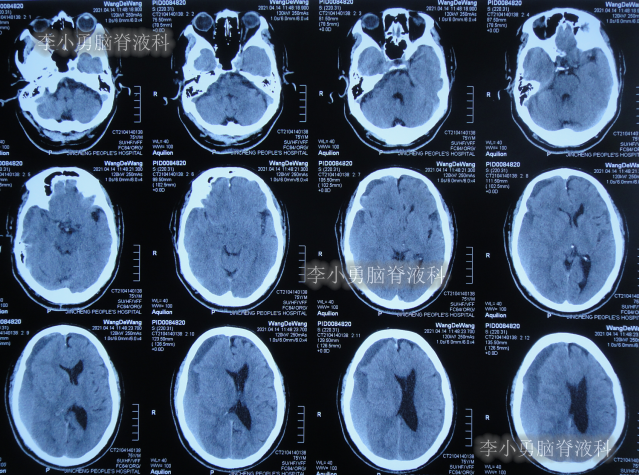

发现脑积水后8天即2020年11月6日,就诊于第2家的上海的某三甲医院,入院后再次检查(图-2)后诊断为正常压力脑积水。

图-2:2020年11月11日头部核磁